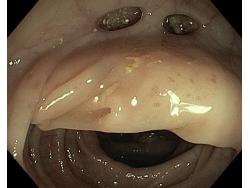

Uchyłki